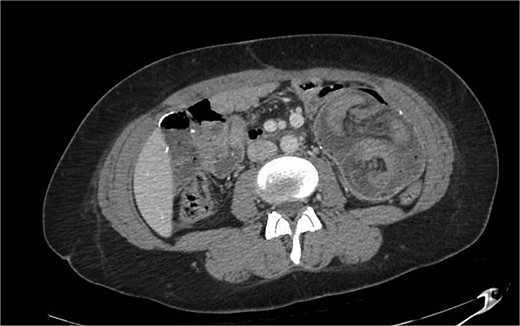

A 28-year-old female with a past medical history of morbid obesity and recurrent intussusception treated with laparoscopic RYGB, laparoscopic revision of jejunojejunostomy, and revision of proximal roux limb reconstituting anastomosis, presented to the emergency department with severe, unremitting abdominal pain. Her index RYGB was performed 6 years prior to presentation and most recent exploratory laparotomy and reconstruction of bypass anatomy occurred ⁓1 year prior. Four years following her RYGB, the patient presented for acute abdominal pain and was found to have intussusception of the jejunojejunostomy necessitating laparoscopic excision of the affected segment with reconstruction of bypass anatomy. Four months after her initial revision, she presented with acute abdominal pain and was found to have a second recurrence of intussusception and required a second laparoscopic excision of jejunojejunostomy with reconstruction of bypass anatomy. On this presentation, physical exam findings were consistent with peritonitis and computed tomography (CT) of her abdomen and pelvis revealed small bowel intussusception in the left abdomen measuring up to 9.6 × 9.1 × 14.7 cm in diameter with decreased enhancement of the small bowel involved in the intussusception concerning for ischemia (Fig. 1). We emergently proceeded to the operating room for diagnostic laparoscopy. On initial investigation, the roux limb reconstituting anastomosis was noted to be healthy appearing; however, there was a long segment of RI of the proximal common channel into the jejunojejunostomy with an obstructed biliopancreatic limb (Fig. 2). This was not reducible and we converted to an open approach for resection and revision of the jejunojejunostomy with reconstruction of the Roux-en-Y anatomy via a stapled, side-to-side antiperistaltic anastomosis between the distal Roux limb and proximal common channel. The patient tolerated the procedure well and has progressed well in the outpatient setting with close monitoring and follow-up.